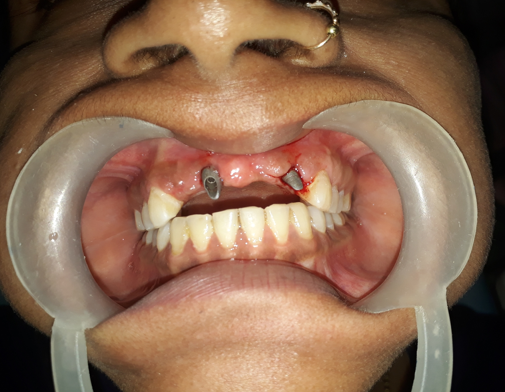

The use of single piece immediate implant (BSC) in the newly extracted area provide better attachment for a basal implant. A flapless immediate implant procedure was used for placing implants. Considering the demands and needs of the patients, It was decided to place a 3.5 mm diameter and 21 mm insertion-length Bicortical screw implant in the edentulous space of maxillary right central and left lateral incisor.([Figure 1])

Metal cutting bur was used for milling the abutment to achieve optimal position and it’s adjustment. Then the flap was covered and sutured. Immediate loading of the implanted area with temporary crown was done.([Figure 2], [Figure 3])